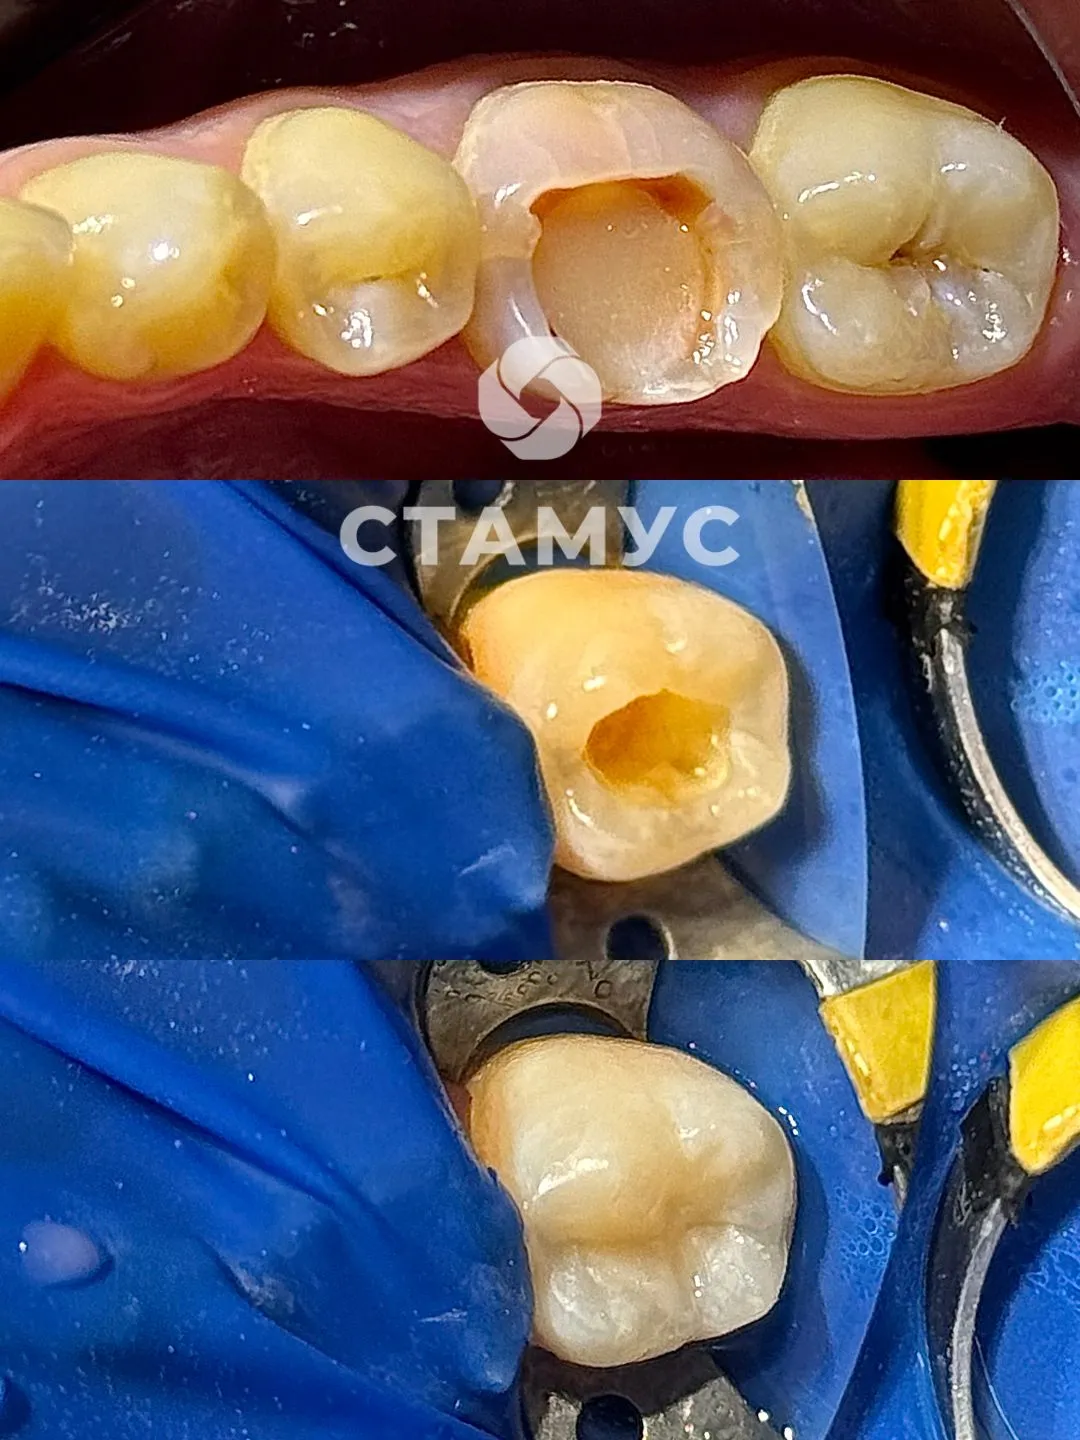

Пациентка, 28 лет. Обратилась с жалобами на реакцию зуба от температурных раздражителей в зубе 37.

При осмотре : выявлен кариозный очаг на жевательной поверхности зуба.

Лечение кариеса и восстановление зуба пломбировочным материалом